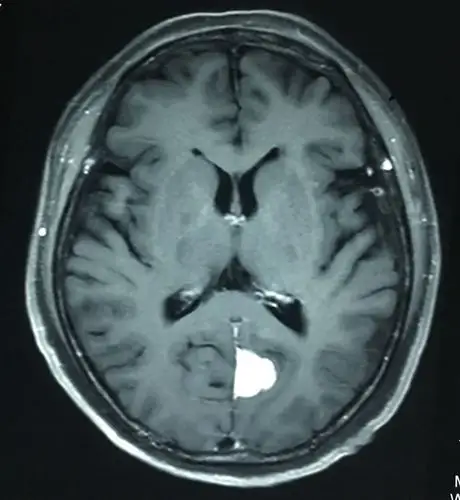

枕部大脑镰良性脑膜瘤 - 好大夫在线